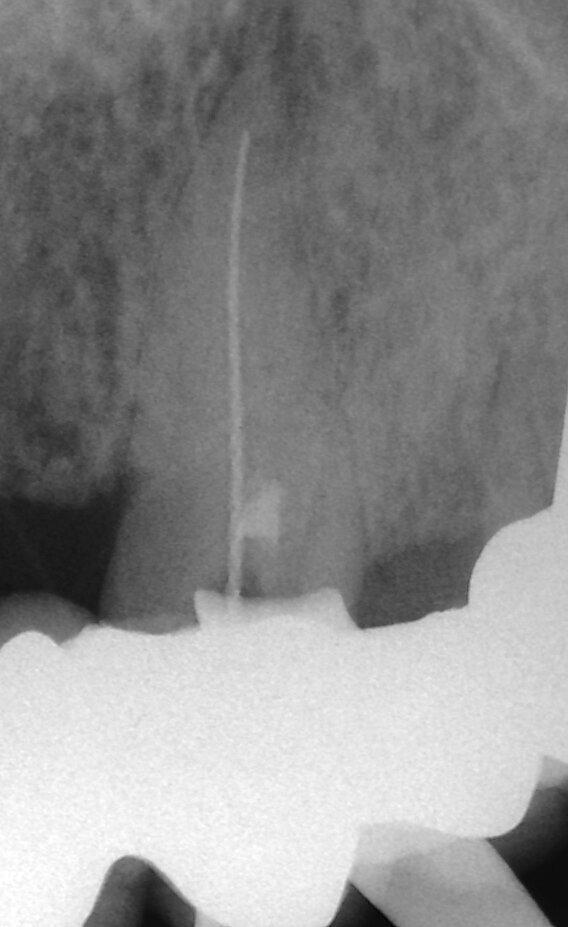

La terapia della polpa vitale è diventata più popolare negli ultimi anni. L’idrossido di calcio è stato il materiale più comune per l’incappucciamento della polpa, ma l’MTA ha mostrato risultati migliori in termini di biocompatibilità e risultati (Aguilar e Linsuwanont 2011). I casi con una grande esposizione della polpa cariosa possono essere trattati con successo con la pulpotomia parziale e l’MTA per l’incappucciamento, mantenendo i denti vitali (Figg. 1a-1e).

L’incappucciamento della polpa, l’apecificazione, la riparazione delle perforazioni radicolari e l’otturazione dei canali radicolari sono comunemente descritti come procedure cliniche per sigillare il percorso di comunicazione tra il sistema canalare radicolare e la superficie esterna del dente. L’applicazione dell’MTA è stata inizialmente ottenuta con l’ausilio di spatole in plastica o metallo (Torabinejad e Chivian 1999). Sfortunatamente non è stato possibile realizzare in tal modo un posizionamento adeguato (Figg. 1a-1e).